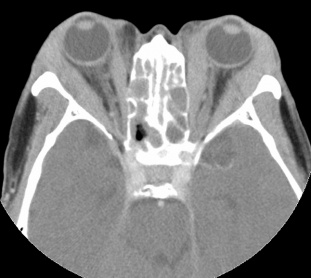

Optic nerve

Inflammatory tissues surrounding an unenhanced optic nerve may demonstrate the classical, "tramline" sign (Figure 4). There may be streaky densities in the contiguous orbital fat.

Figure 4: CT image of optic nerve involvement with sheath enhancement ("tramline" sign) (asterisks), white arrow showing right lacrimal gland enlargement. (Courtesy of Z.X. Ding).